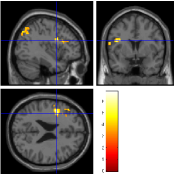

Once the reduced FOV images are available, the proposed pMRI 4D-UWR-SENSE algorithm and its early UWR-SENSE version have been utilized in a final step to reconstruct the full FOV EPI images and compared to the mSENSE Siemens solution. For the wavelet-based regularization, dyadic Symmlet orthonormal wavelet bases [48] associated with filters of length 8 have been used over resolution levels. The reconstructed EPI images then enter in our fMRI study in order to measure the impact of the reconstruction method choice on brain activity detection. Note also that the proposed reconstruction algorithm requires the estimation of the coil sensitivity maps (matrix in Eq. (2)). As proposed in [4], the latter were estimated by dividing the coil-specific images by the module of the Sum Of Squares (SOS) images, which are computed from the specific acquisition of the -space centre (24 lines) before the scans. The same sensitivity map estimation is then used for all the compared methods. Fig. 5 compares the two pMRI reconstruction algorithms to illustrate on axial, coronal and sagittal EPI slices how the mSENSE reconstruction artifacts have been removed using the 4D-UWR-SENSE approach. Reconstructed mSENSE images actually present large artifacts located both at the centre and boundaries of the brain in sensory and cognitive regions (temporal lobes, frontal and motor cortices, …). This results in SNR loss and thus may have a dramatic impact for activation detection in these brain regions. Note that these conclusions are reproducible across subjects although the artifacts may appear on different slices (see red circles in Fig. 5). One can also notice that some residual artifacts still exist in the reconstructed images with our pipeline especially for . Such strong artifacts are only attenuated and not fully removed because of the high level of information loss at .

| mSENSE | 4D-UWR-SENSE | ||

| Axial |  |

|

|

| Coronal | |||

| Sagittal | |||

| Axial |  |

|

|

| Coronal | |||

| Sagittal |